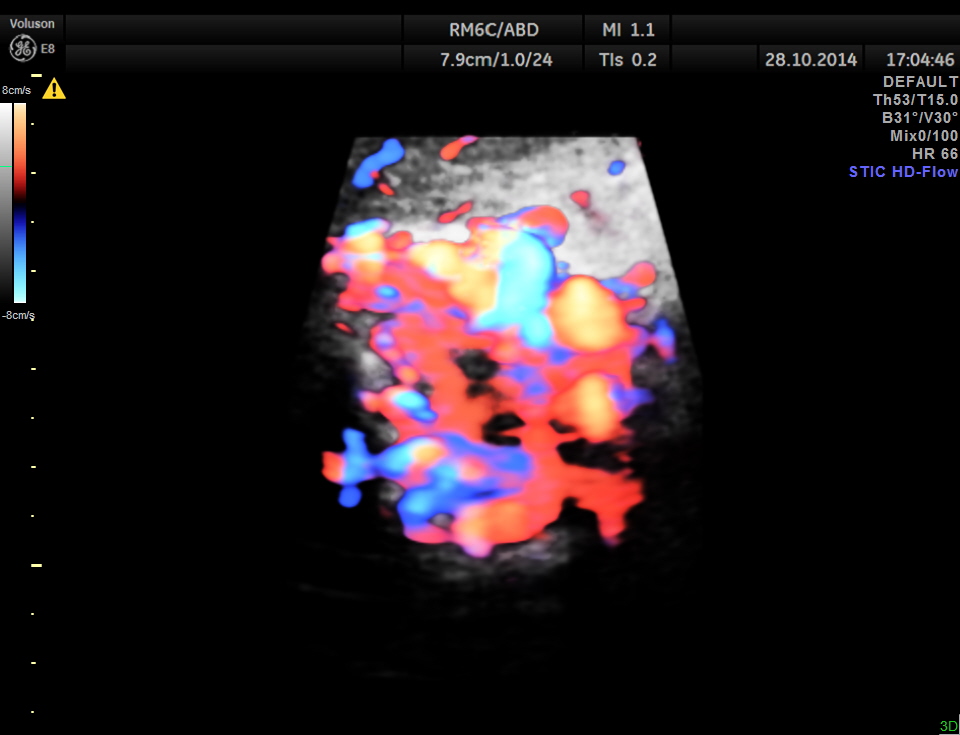

STIC HD flow image.